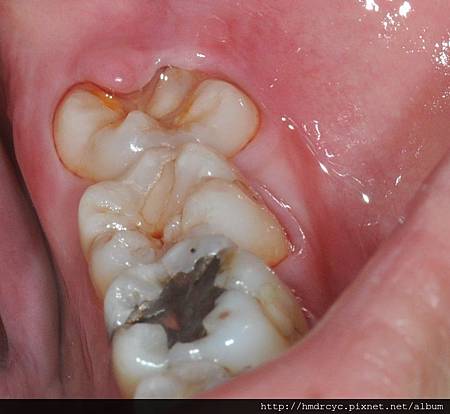

當智齒長歪頂到前面的牙齒

細菌跑進來的時候會無法清潔

頂到前面牙齒的地方會蛀牙

而牙肉包住的地方會牙肉發炎牙周病